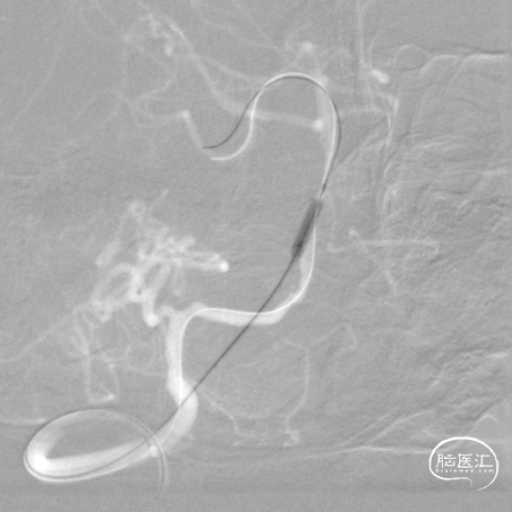

将微导丝头端置右侧大脑后动脉,沿微导丝引入2.0*10mm球囊,小心扩张狭窄段,撤出球囊后造影,原有狭窄较前稍好转,沿微导丝引入支架用微导管置于基底动脉,撤出微导丝,保留微导管,沿微导管引入3.5*15mm Neuroform EZ支架,缓慢释放,复查造影,狭窄较前明显好转,支架贴壁良好。

复查Dyna CT,颅内未见出血及造影剂外渗。